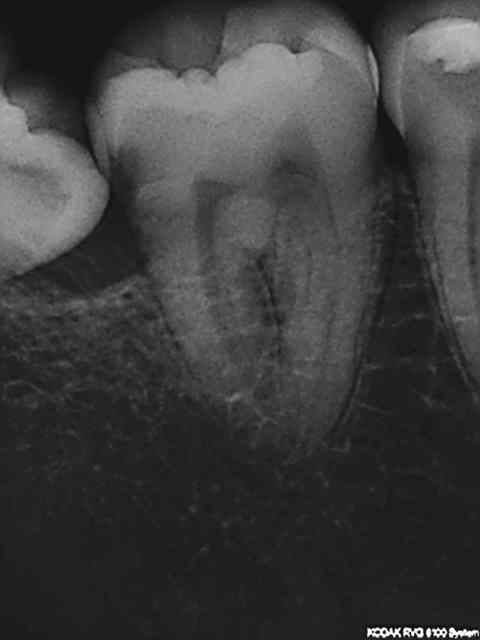

Radio initiale, cone en place , cone scellé, radio du bouchon apical réalisé au système b, puis radio finale après thermo-condensation. C'est obligatoire avec la nouvelle CCAM. Fini de jouer au dentiste le 1er juin.)))))))

Elles sont dans le désordre , remets les en ordre ( ca fait partie d'un qcm de formation continue) vu que le niveau de la formation initiale semble resté bloqué dans les années 80.